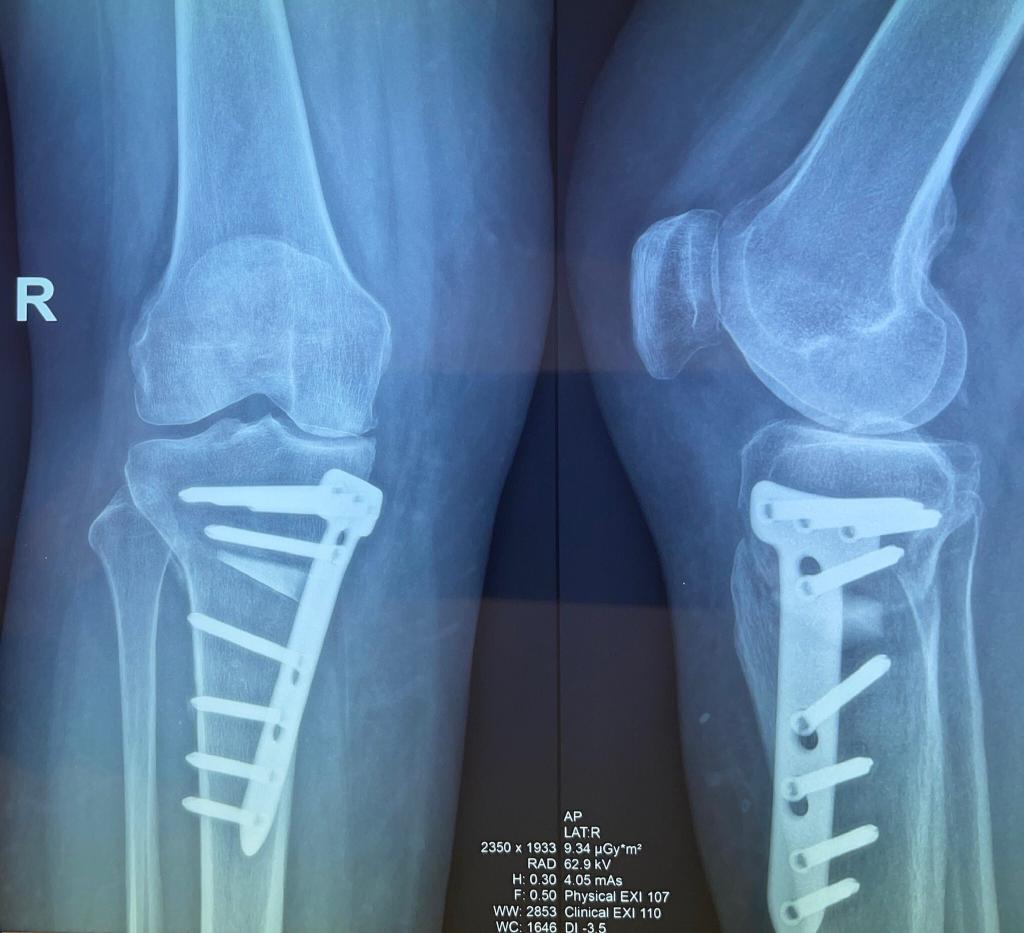

- Când durerea persistentă și limitarea funcțională nu răspund la tratamentele conservatoare și leziunile sunt avansate, se ia în considerare opțiunea chirurgicală, în cadrul unei decizii partajate cu echipa medicală.